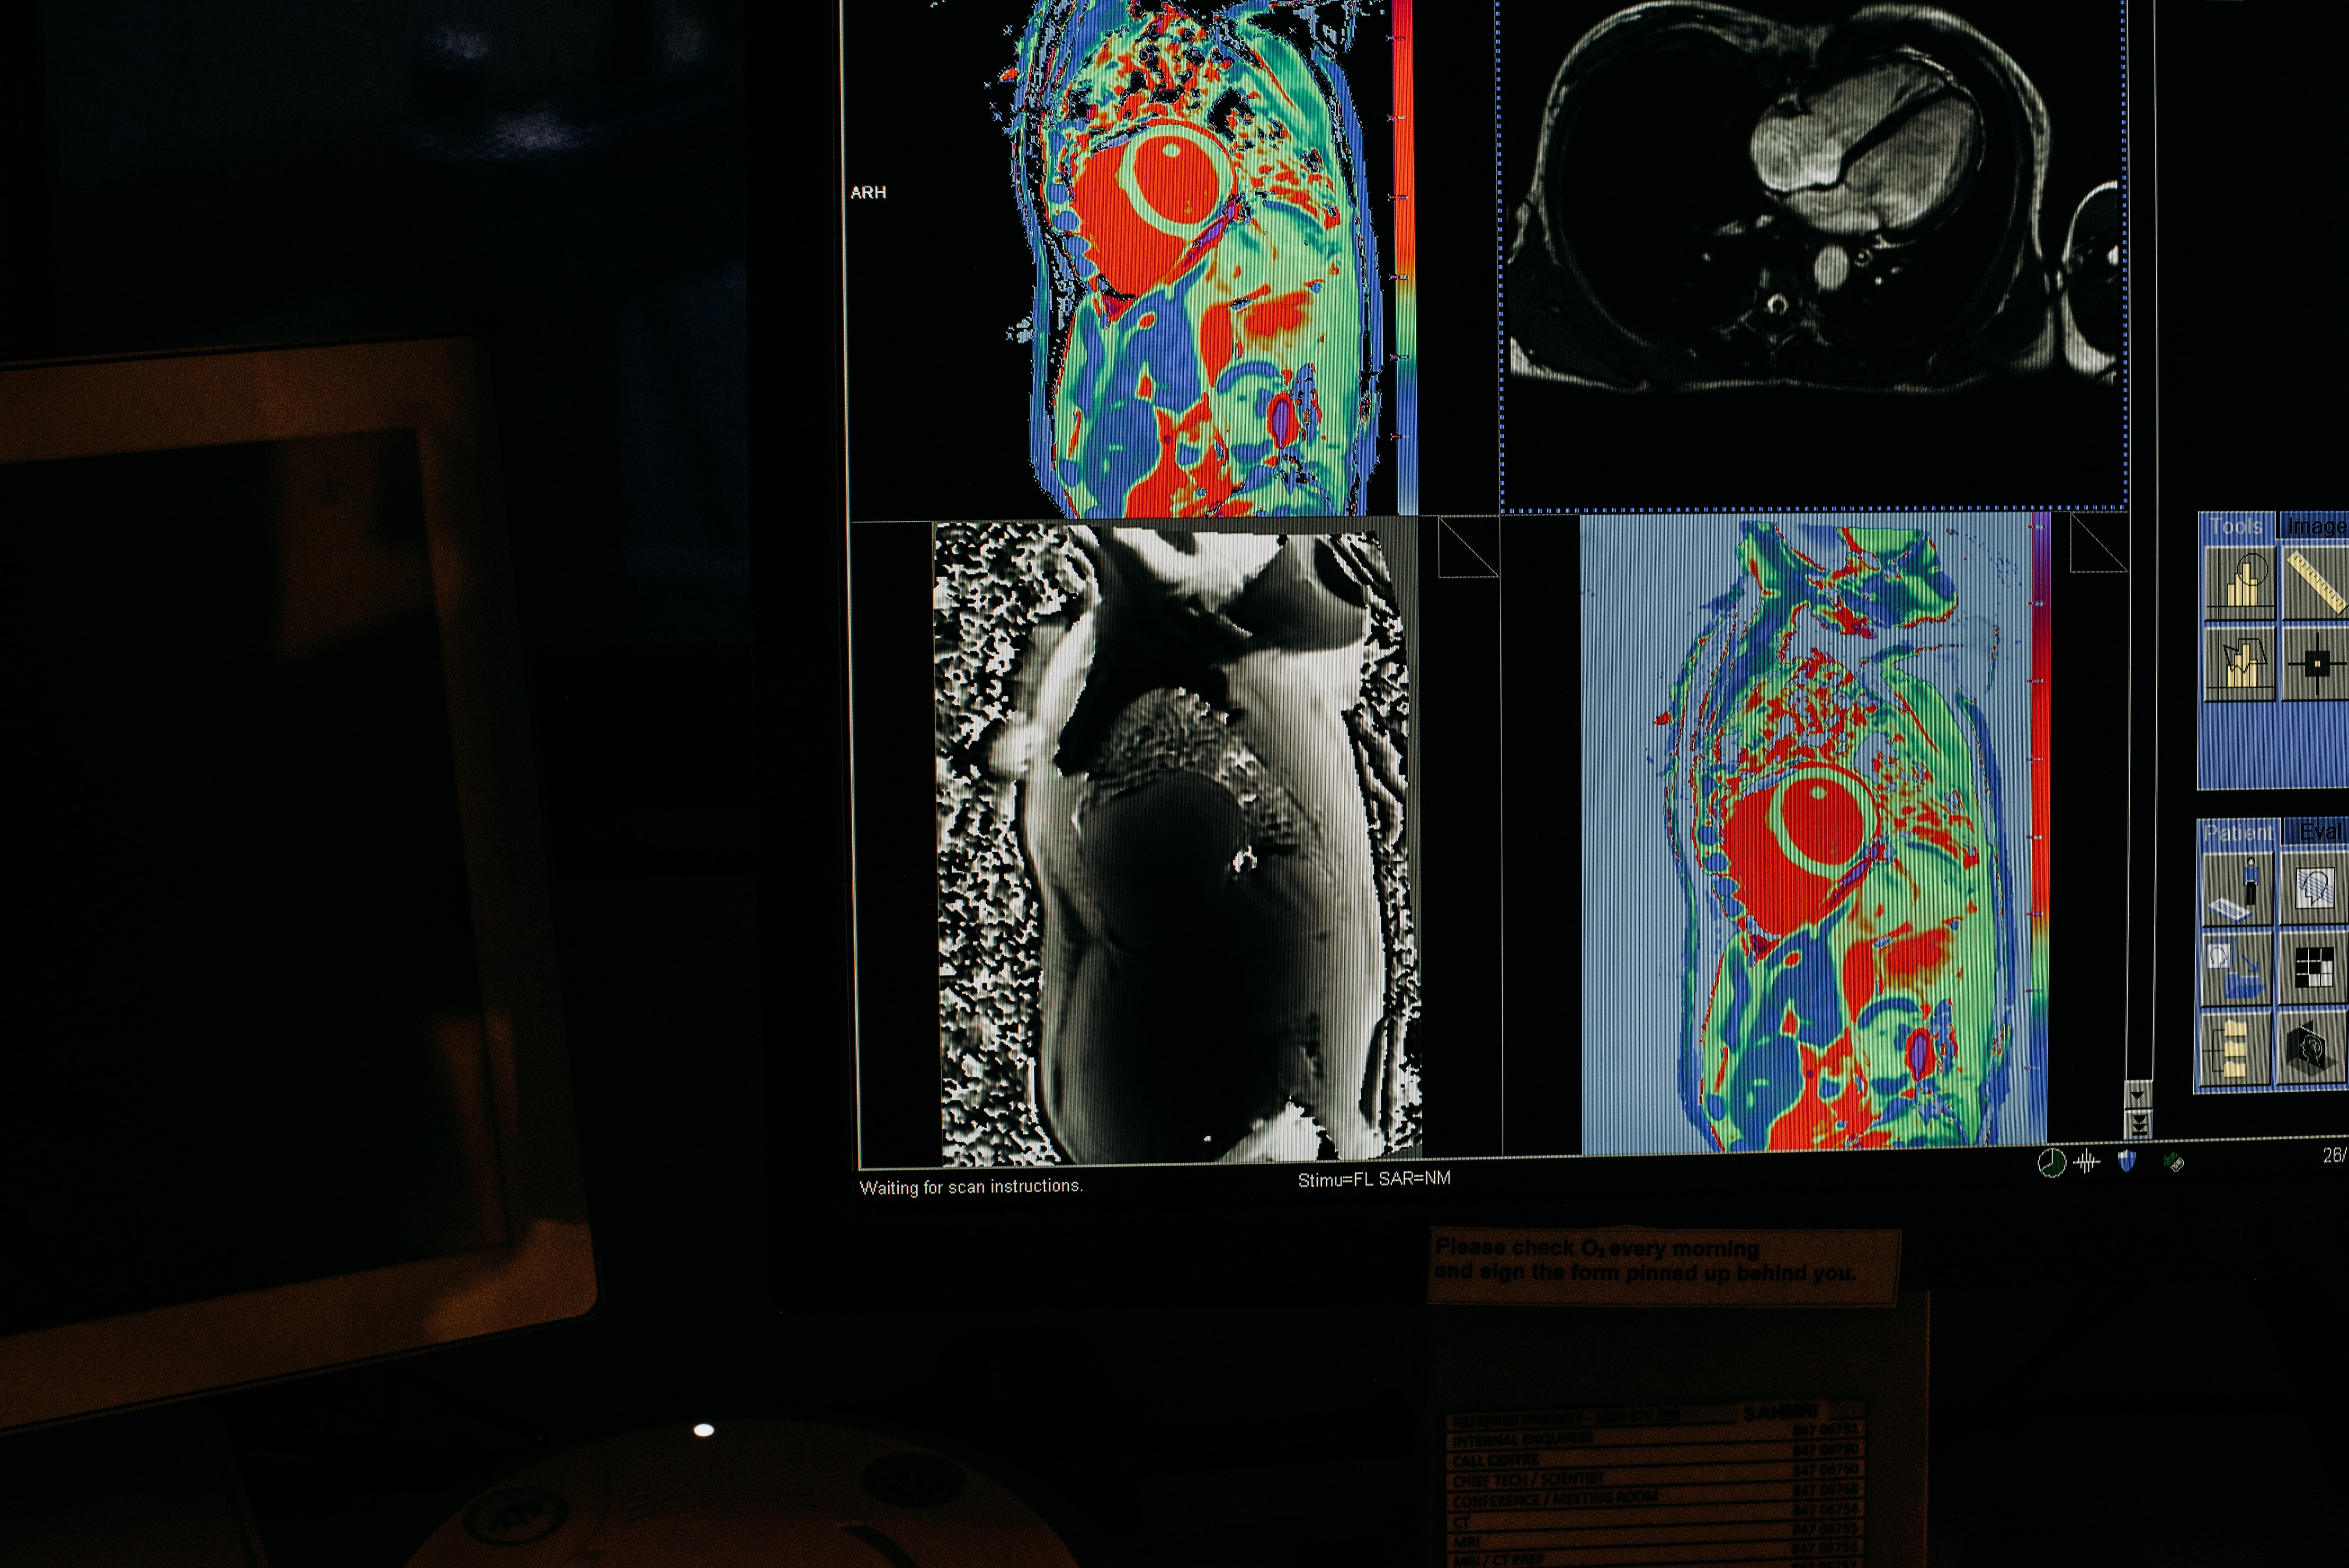

SAHMRI’s research relies on a variety of imaging technologies including x-ray, ultrasound, CT, MRI and PET scanning at the co-located Clinical and Research Imaging Centre and small, medium and large animal scanning at the Preclinical, Imaging and Research Laboratories site at Gilles Plains. The Molecular Imaging and Therapy Research Unit at SAHMRI also produces daily doses of radiopharmaceuticals which are essential for clinical and research imaging.